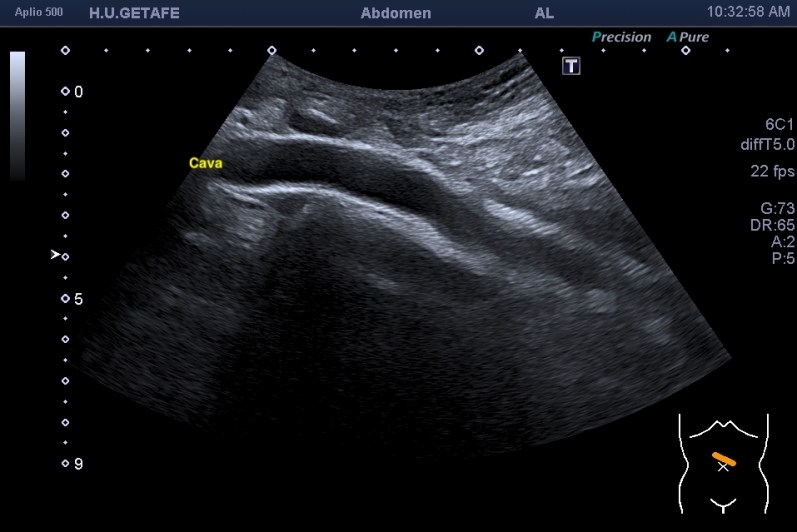

Lo que ves en estas imágenes que te voy a poner aquí son los hallazgos ecográficosque he podido visualizar hoy. Los voy a complementar con la correlación con las imágenes de TAC. En este caso específico con la eco solo se pudo corroborar los hallazgos del escáner, que a nivel anatómico arroja un mejor desarrollo de la anatomía regional implicada en el proceso.

6En el corte longitudinal de la imagen 1 ya se ve una vaso perimetrado por una imagen hiperecogénica, no compresible a la presión con la sonda convexa. En la imagen 2 con la sonda lineal se observa el enrejado habitual de los stents, que en otras ocasiones ya hemos comentado en otro post en localización distinta.